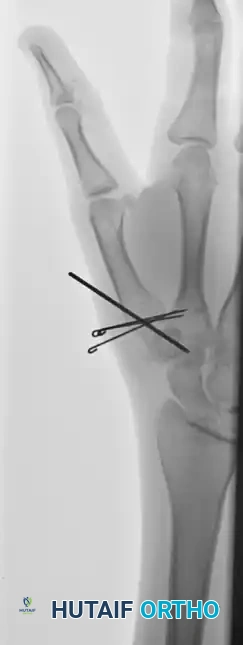

While an assistant (or the surgeon's non-dominant hand) maintains the reduction, the pinning is executed:

* Drill a 0.045-inch or 0.062-inch Kirschner wire into the base of the metacarpal.

* Direct the wire proximally across the CMC joint and into the body of the trapezium.

Surgical Warning: Fixation merely to the volar oblique fragment is often insufficient to prevent the loss of fracture reduction. The K-wire must engage the trapezium to neutralize the deforming forces of the APL.

Sometimes, more than one Kirschner wire is required to achieve absolute rotational stability. Depending on the fracture geometry, the secondary wire may engage carpal bones other than the trapezium (such as the trapezoid or the capitate) for adequate fixation.